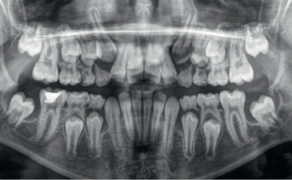

Streszczenie: Wprowadzenie. Założenie elastomerowych separatorów ortodontycznych może być dla pacjenta bolesne i powodować dyskomfort. Aby wizyta ortodontyczna odbyła się bez problemów, ważne jest złagodzenie tego nieprzyjemnego uczucia. Celem niniejszej pracy było zbadanie wpływu miejscowego znieczulenia lidokainą z prylokainą na ból i dyskomfort związany z założeniem elastomerowych separatorów ortodontycznych. Materiał i metoda. W badaniu wzięło udział pięćdziesiąt osób w wieku 20-35 lat. Po jednej stronie górnego łuku zębowego aplikowano na brzegi dziąseł wokół zęba przedtrzonowego i trzonowego miejscowy środek znieczulający w postaci lidokainy z prylokainą. Po drugiej stronie w tym samym miejscu nanoszono placebo. Po dwóch minutach obustronnie pomiędzy zębem przedtrzonowym i trzonowym zakładano separator elastomerowy. Następnie badanych poproszono, aby notowali swoje odczucia w skali werbalnej i wizualnej co dwie minuty przez 10 minut. Otrzymali oni również kwestionariusz mający ocenić ogólne wrażenia z zastosowania znieczulenia miejscowego. Wyniki. Całkowita średnia wartość punktowa odczucia dyskomfortu/bólu okazała się znamiennie niższa (p < 0,001) w przypadku znieczulenia miejscowego niż w przypadku placebo. Powtarzane analizy ANOVA z korektą Greenhouse’a-Geissera wykazały, że średnie wartości bólu były statystycznie [...]